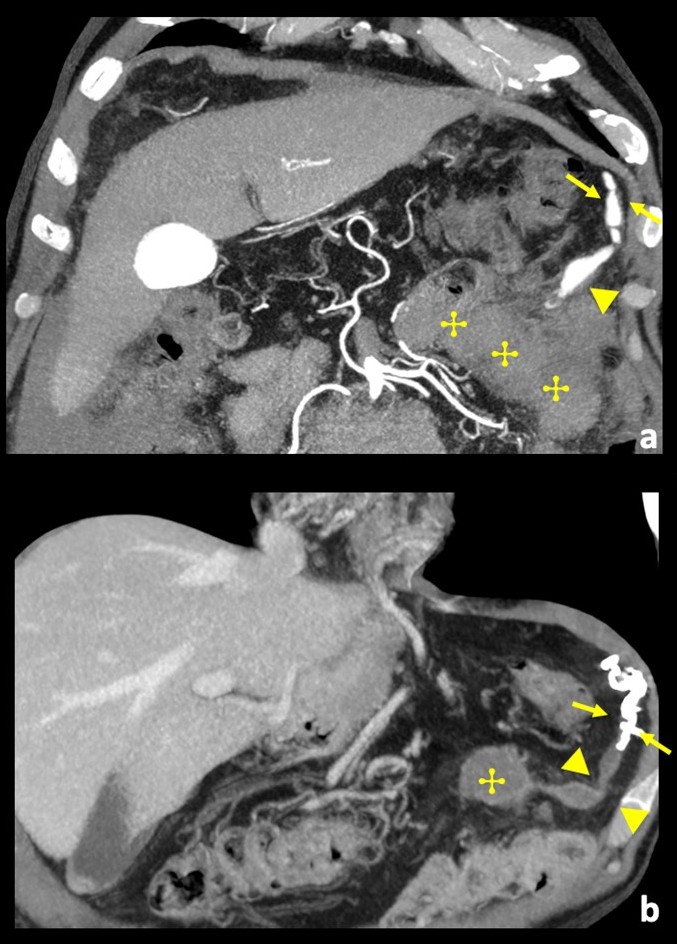

Figure 3: Comparison between contrast-enhanced coronal angio-CT MIP reconstruction pre-procedure (a), and, coronal image at the same level 1-month after embolization (b). (a) A long ectatic vessel with multilobulated aneurysms can be seen (arrow). (b) Corresponding image after embolization shows spontaneous thrombosis of the more distal and bigger aneurysmal sac (arrowhead) and hyperdense rich embolic material just upstream (arrow), corresponding to angiographic diagnostic image; there was hematoma re-absorption (✣), and there was no mass underlying.

One month after the procedure, the patient's hemoglobin increased to 12.8 g/dl. Follow up abdominal CT showed adequate embolization of the anomalous and ectatic segment of the left gastroepiploic artery, with hematoma retaining identical dimensions. The patient is under long-term outpatient clinical surveillance.(Fig. 3)